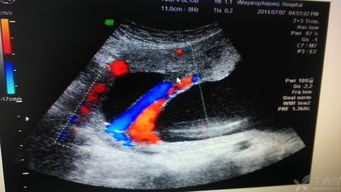

血流信号,即血流的丰富程度。

血流丰富程度的分级通常分为四级:

0级为肿块内未见血流信号显示;

1级为少量血流,肿块内见1~2个点状血流信号;

2级为中量血流,肿块内见3~4个点状血流信号或一条管壁清晰的血管;

3级为丰富血流,肿块内见4个以上点状血流或2条管壁清晰的血管。

一般来说,恶性肿块的血供较良性肿块丰富,前者多为2~3级血流,后者多为0~1级血流。肿瘤中,恶性组2~3级血流的占86.96%,良性组0~1级血流的占91.3%。

虽然血流丰富程度与良恶性有关,但与肿块的大小亦有一定的关系。一些较大的乳腺良性肿块内可观察到丰富的血流信号,而在一些小乳腺癌内却未见血流信号显示,这可能与肿瘤体积小,新生血管相对较少且管径较细,以及仪器的灵敏度的局限性,以致细小血管的低速血流难以显示等因素有关。

CDFI显示人体的血流,二、三维超声成像显示人体的解剖结构,二者提供了完整的人体解剖信息。以CDFI为基础,由于CDFI不需要方向分离、频域解调等处理,可降低检测阈值,便于显示小血管中的低速血流,但不能区分流向和流速。